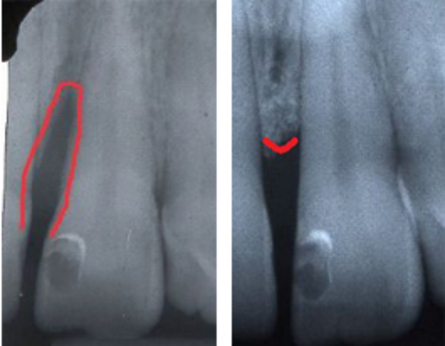

Nei casi di parodontite avanzata, il tessuto osseo e gengivale che sostiene gli elementi dentari è danneggiato e le tasche parodontali (gli spazi tra dente e gengiva) si approfondano creando uno spazio più ampio dove i batteri possono proliferare. In questi casi i trattamenti di levigatura radicolare o di igiene orale professionale non sono più sufficienti.

Qualora non si intervenisse chirurgicamente, l’osso alveolare tenderebbe a riassorbirsi a causa del continuo insulto batterico e, qualora questa perdita fosse notevole, l’estrazione potrebbe essere l’unica terapia possibile. Anche se il paziente ha un’ottima igiene orale, la terapia chirurgica è indicata poiché le manovre di igiene domiciliare non permettono di posizionare le setole dello spazzolino al di sotto della gengiva per più di 0.8 mm.

L’approccio chirurgico chirurgia osseo resettiva consiste nel rimuovere il tessuto malato (la tasca) e nel ricontornare i tessuti molli (gengive) e duri (osso alveolare) rendendone uniforme l'alteza e rimuovendo picchi e irregolarità. Eliminando le anomalie del tessuto osseo e gengivale che determinano un'accumulo di placca è possibile infatti ottenere un’anatomia che permetta l’eliminazione permanente delle tasche, dei difetti ossei e di favorire le manovre di igiene domiciliare.